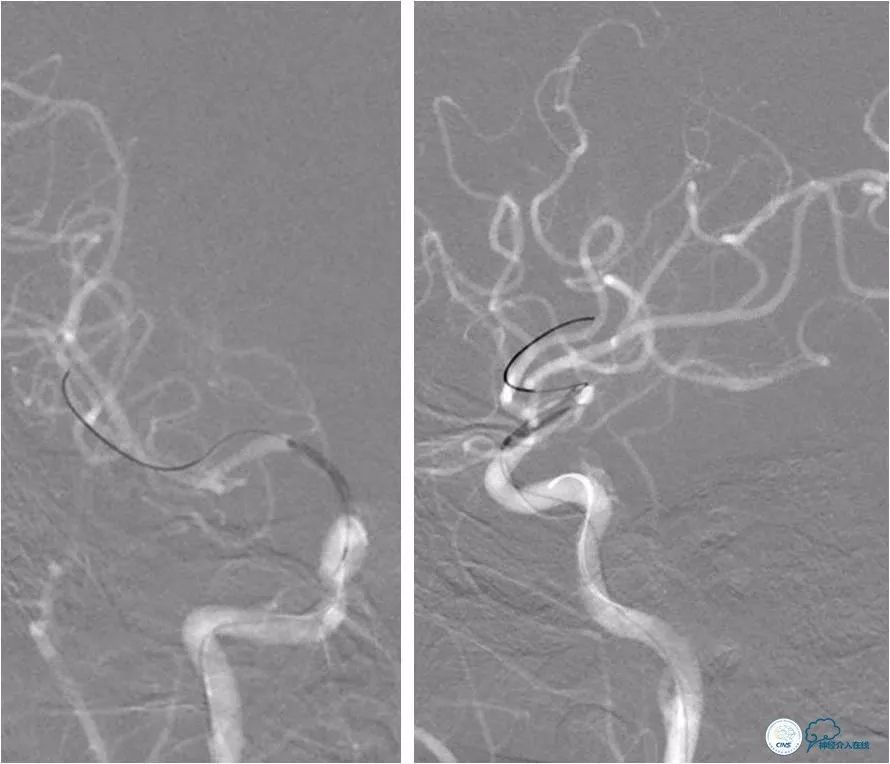

全麻下右股动脉入路,将6F导引导管放至右颈内动脉C1段远端,造影示右颈内动脉C7段重度狭窄(图6)。

图6

路径图下将Transend微导丝(0.014″,300cm)至右大脑中动脉M3段,沿微导丝送入Gateway球囊(2.0mm×15mm)于狭窄处扩张(图7)。

图7

撤出球囊导管,后沿微导丝送入Wingspan自膨式支架(3.0mm×15mm),期间将导引导管送至右颈内动脉C3段,以增加系统支撑力(图8)。

图8